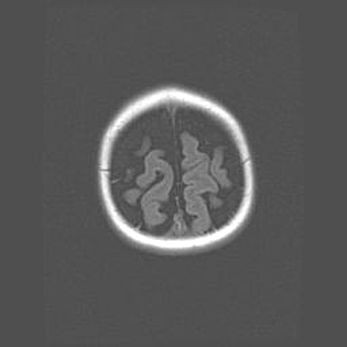

Открытая гидроцефалия.

Возраст: 6 месяцев 15 дней

Вес: 6200 г

Пол: женский

Окружность головы: 41 см

Срок гестации: 38 недель

Гидроцефалия головного мозга у новорожденных – это скопление избыточного количества цереброспинальной жидкости в головном мозге. Ее избыточное скопление в мозге приводит к патологическому расширению желудочков мозга (четырех полостей, расположенных в глубине белого вещества мозга, заполненных цереброспинальной жидкостью и связанных узкими проходами).

Открытый тип гидроцефалии (сообщающаяся) наблюдается тогда, когда нарушен механизм всасывания ликвора в системный кровоток. При этом типе причиной заболевания чаще всего является перенесенные ранее инфекции (например: менингит),  либо же наличие крови в субарахноидальном пространстве.